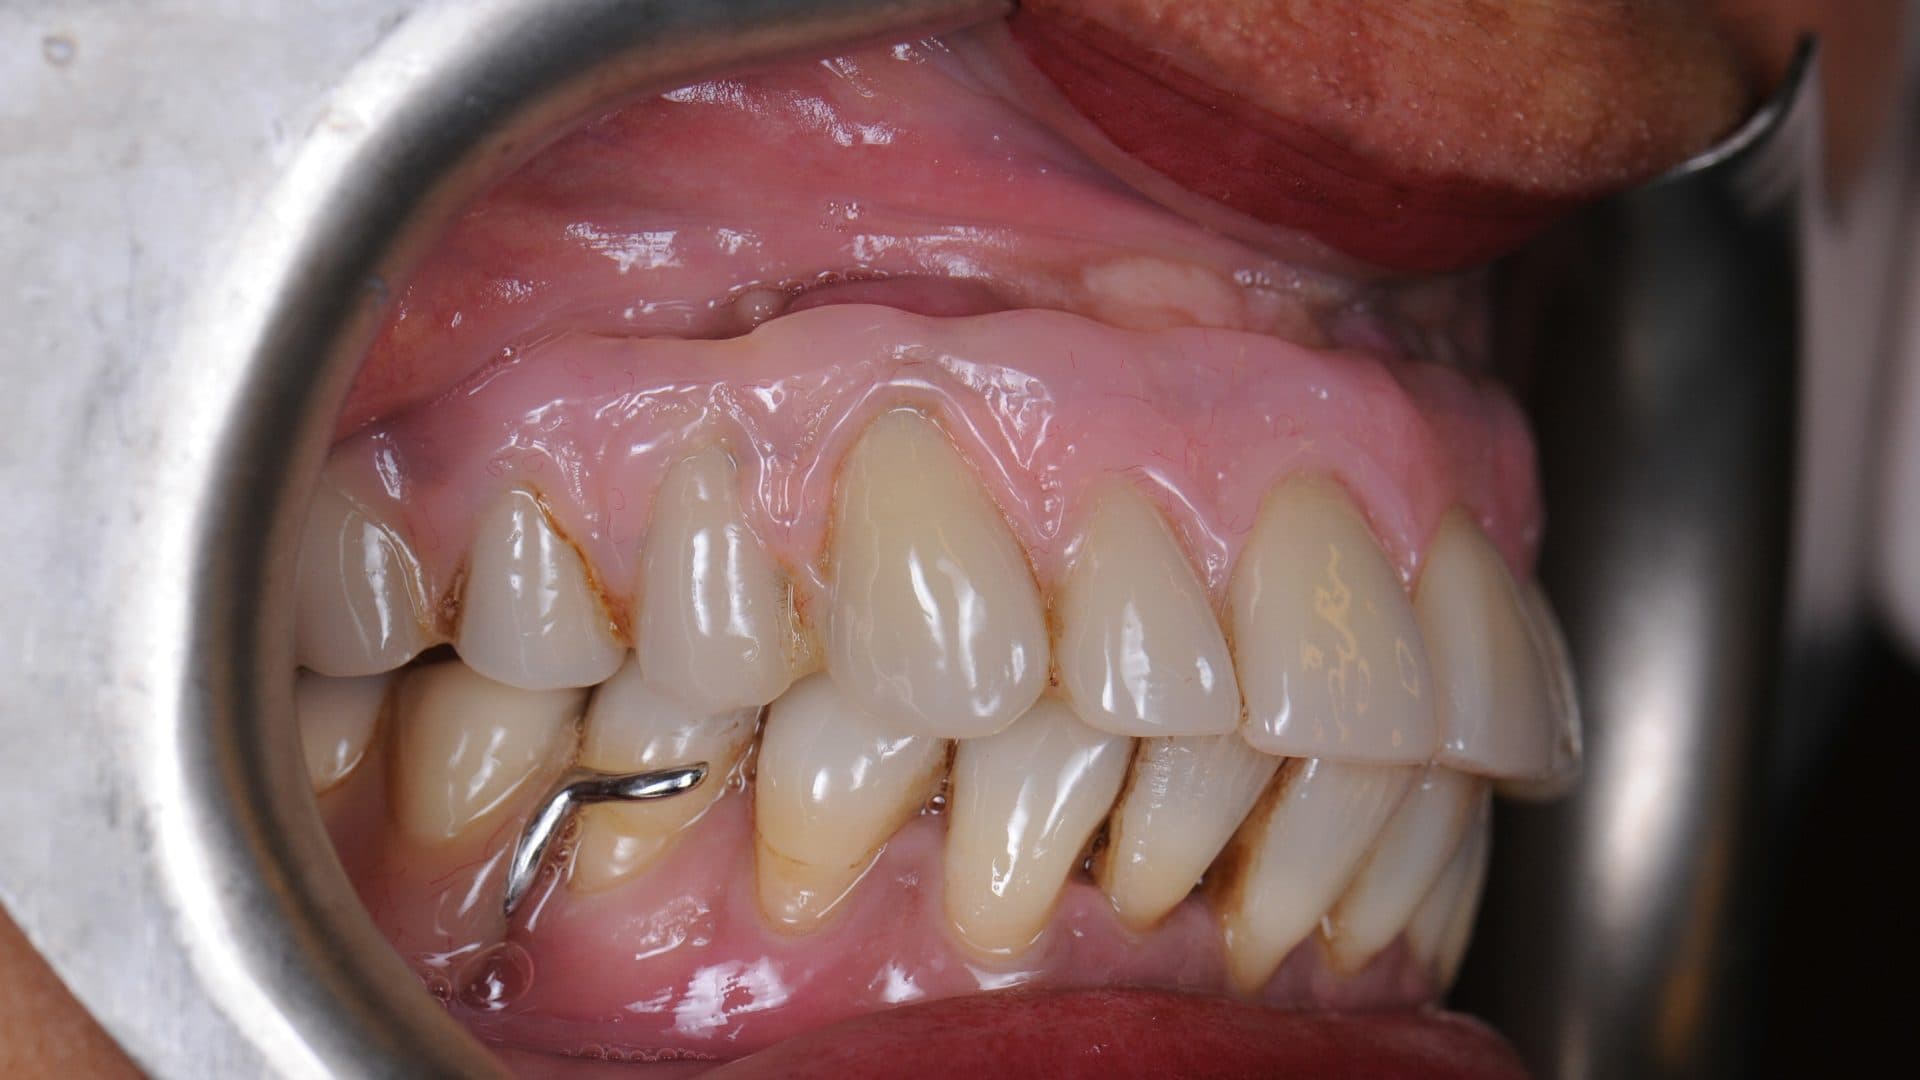

i. Even spread of the implants and flat and uniform under-surface/interface between the prosthesis and the natural gums. A deviation from this will affect the cleanability of the prosthesis, food entrapment and smell (See pictures);

Examples Of Poor Standards

ii. The access holes for the screws are located near the edges of the front teeth and in the middle of the back teeth. Any deviation from this will severly affect level of comfort, speech, and also cleanability (See pictures);